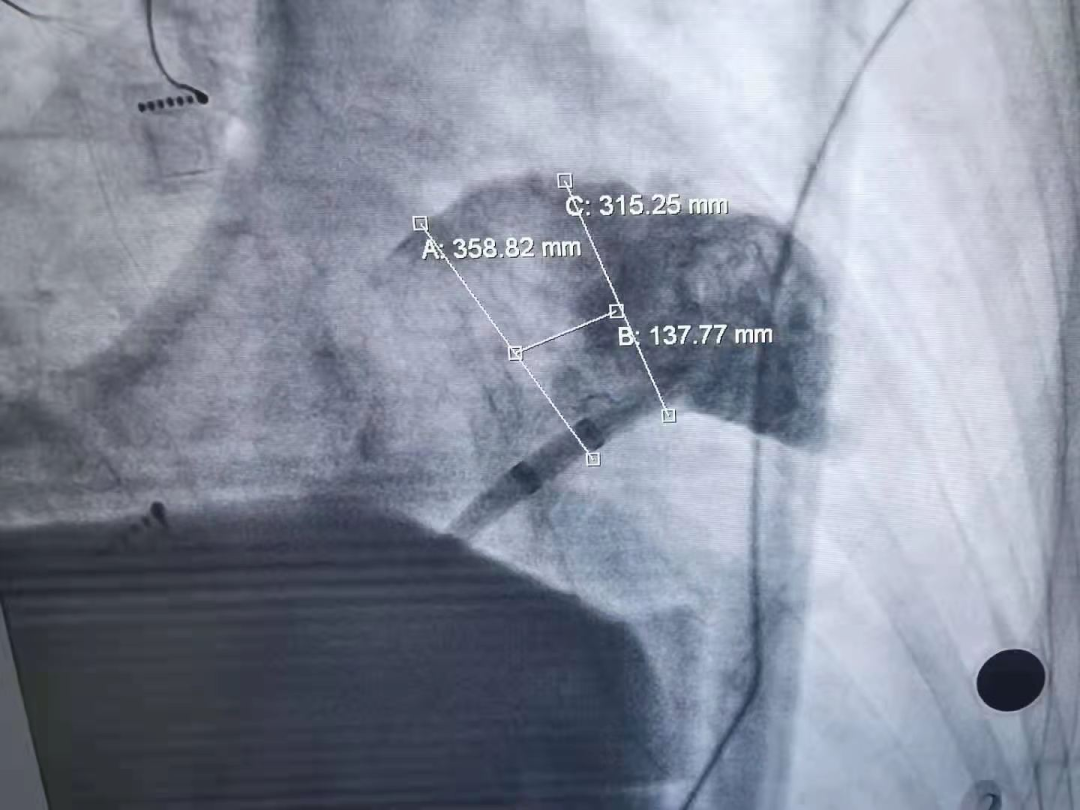

X射线下造影测量左心耳大小(两个体位分别为外30mm,内25mm和外35mm,内31mm)